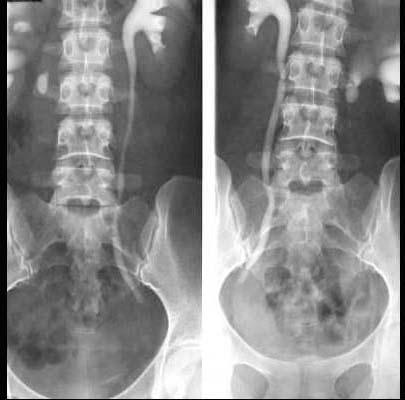

问题 关于输尿管结石,下列哪项是错误的 ( )

选项 A、一侧输尿管结石、对侧肾结石,应先处理对肾功能影响较大的肾结石 B、结石常停留或嵌顿于肾盂输尿管连接处、输尿管跨越髂血管处及输尿管膀胱连接处 C、输尿管结石多继发于肾结石 D、结石位于输尿管下1/3处最为多见 E、结石以上输尿管部分常有扩张

答案 A